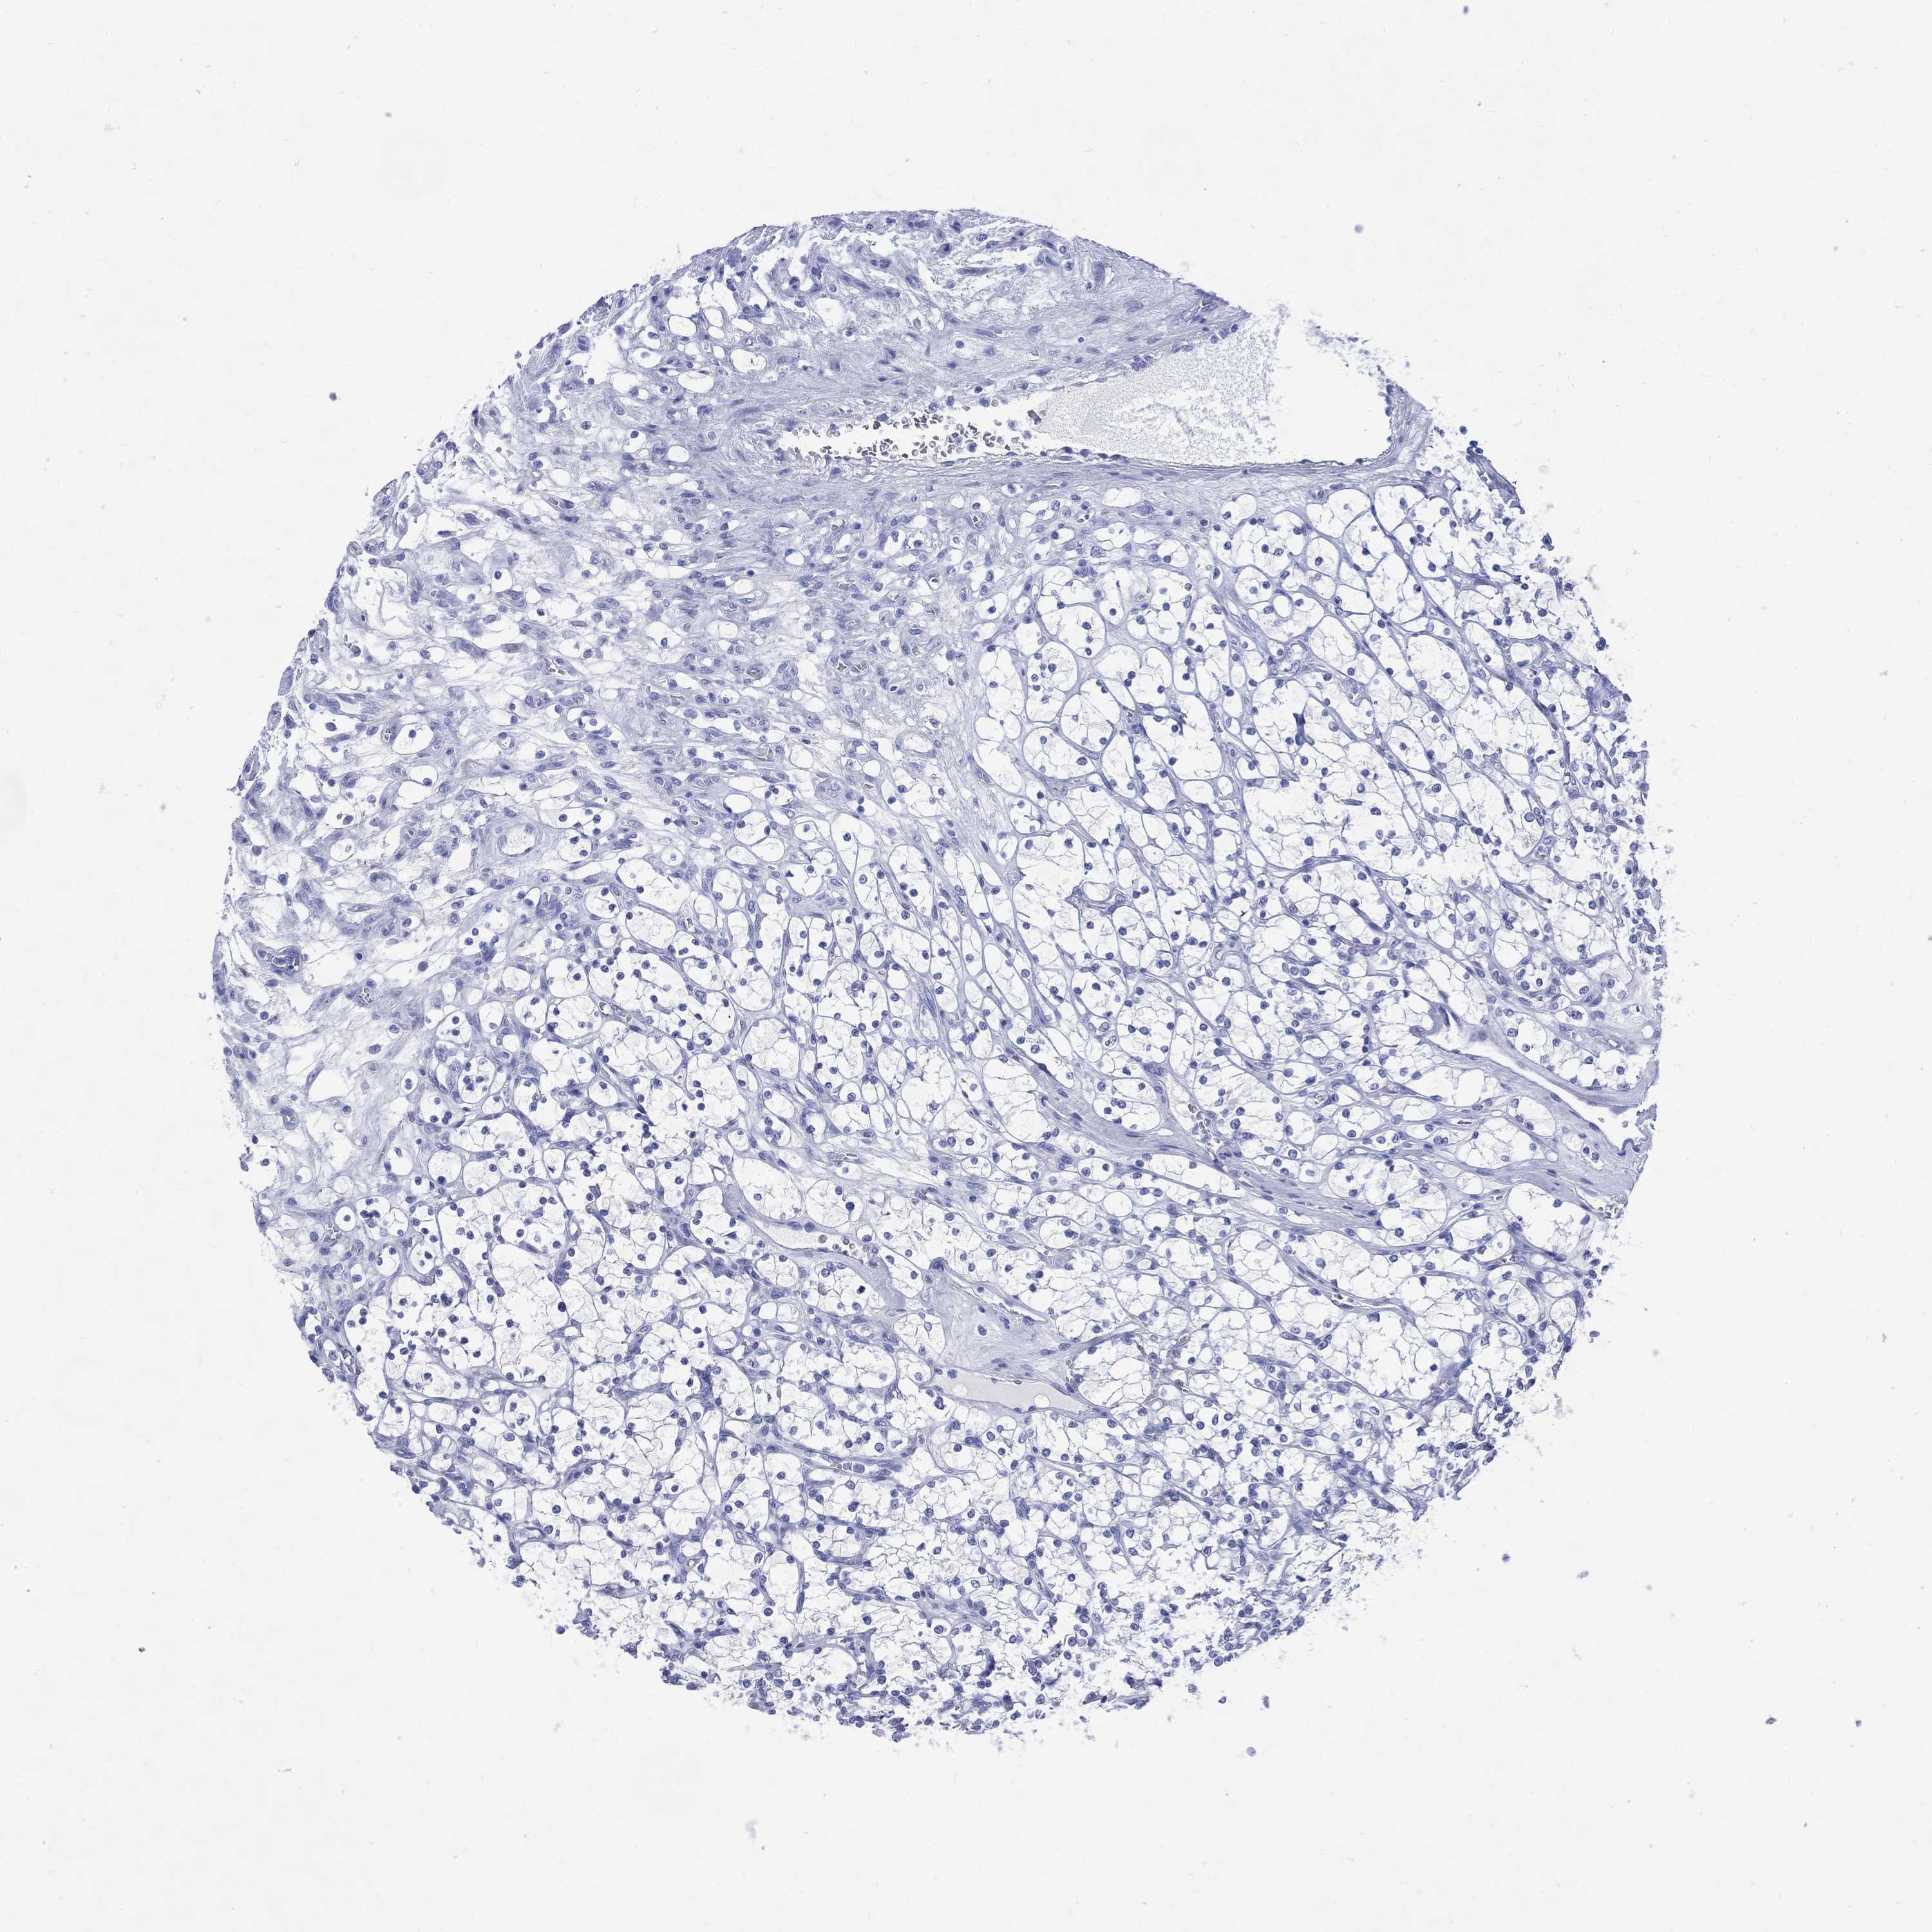

TCGA RNA samplesi

RNA-seq data is reported as average FPKM (number Fragments Per Kilobase of exon per Million reads), generated by the The Cancer Genome Atlas (TCGA) .

Normal distribution across the dataset is visualized with box plots, shown as median and 25th and 75th percentiles. Points are displayed as outliers if they are above or below 1.5 times the interquartile range. FPKM values of the individual samples are presented next to the box plot.

Average pTPM 0.0

Number of samples 100